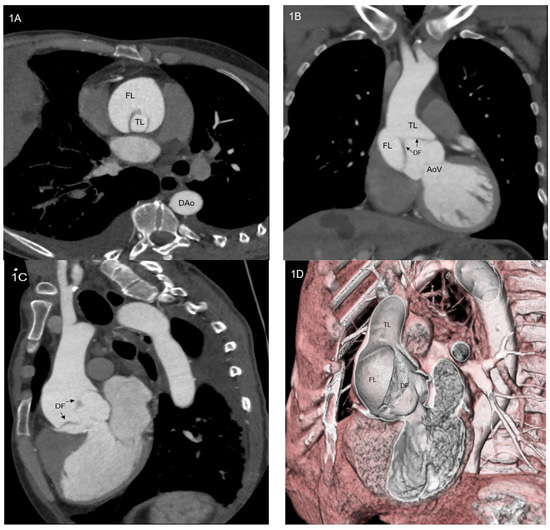

These data could underestimate the real incidence of thoracic aortic dissection, since the hospital-based registries account only for patients who arrived alive at the emergency department, whereas almost 50% of subjects with type A aortic dissection (TAAD, Figure 1A–D) die before hospital admission. Furthermore, a British study suggests that among patients with aortic dissection the proportion of subjects aged over 75 years old will reach 49.7% in 2030 and 57.3% by 2050. This is mainly due to ageing and resistant hypertension [4].

Figure 1.

(A–D) Computed tomography angiogram of a patient with type A aortic dissection: axial scan (A), coronal scan (B), sagittal scan (C) and 3D volume rendering view. AoV = aortic valve; DAo = descending aorta; DF = dissection flap; FL = false lumen; TL = true lumen.